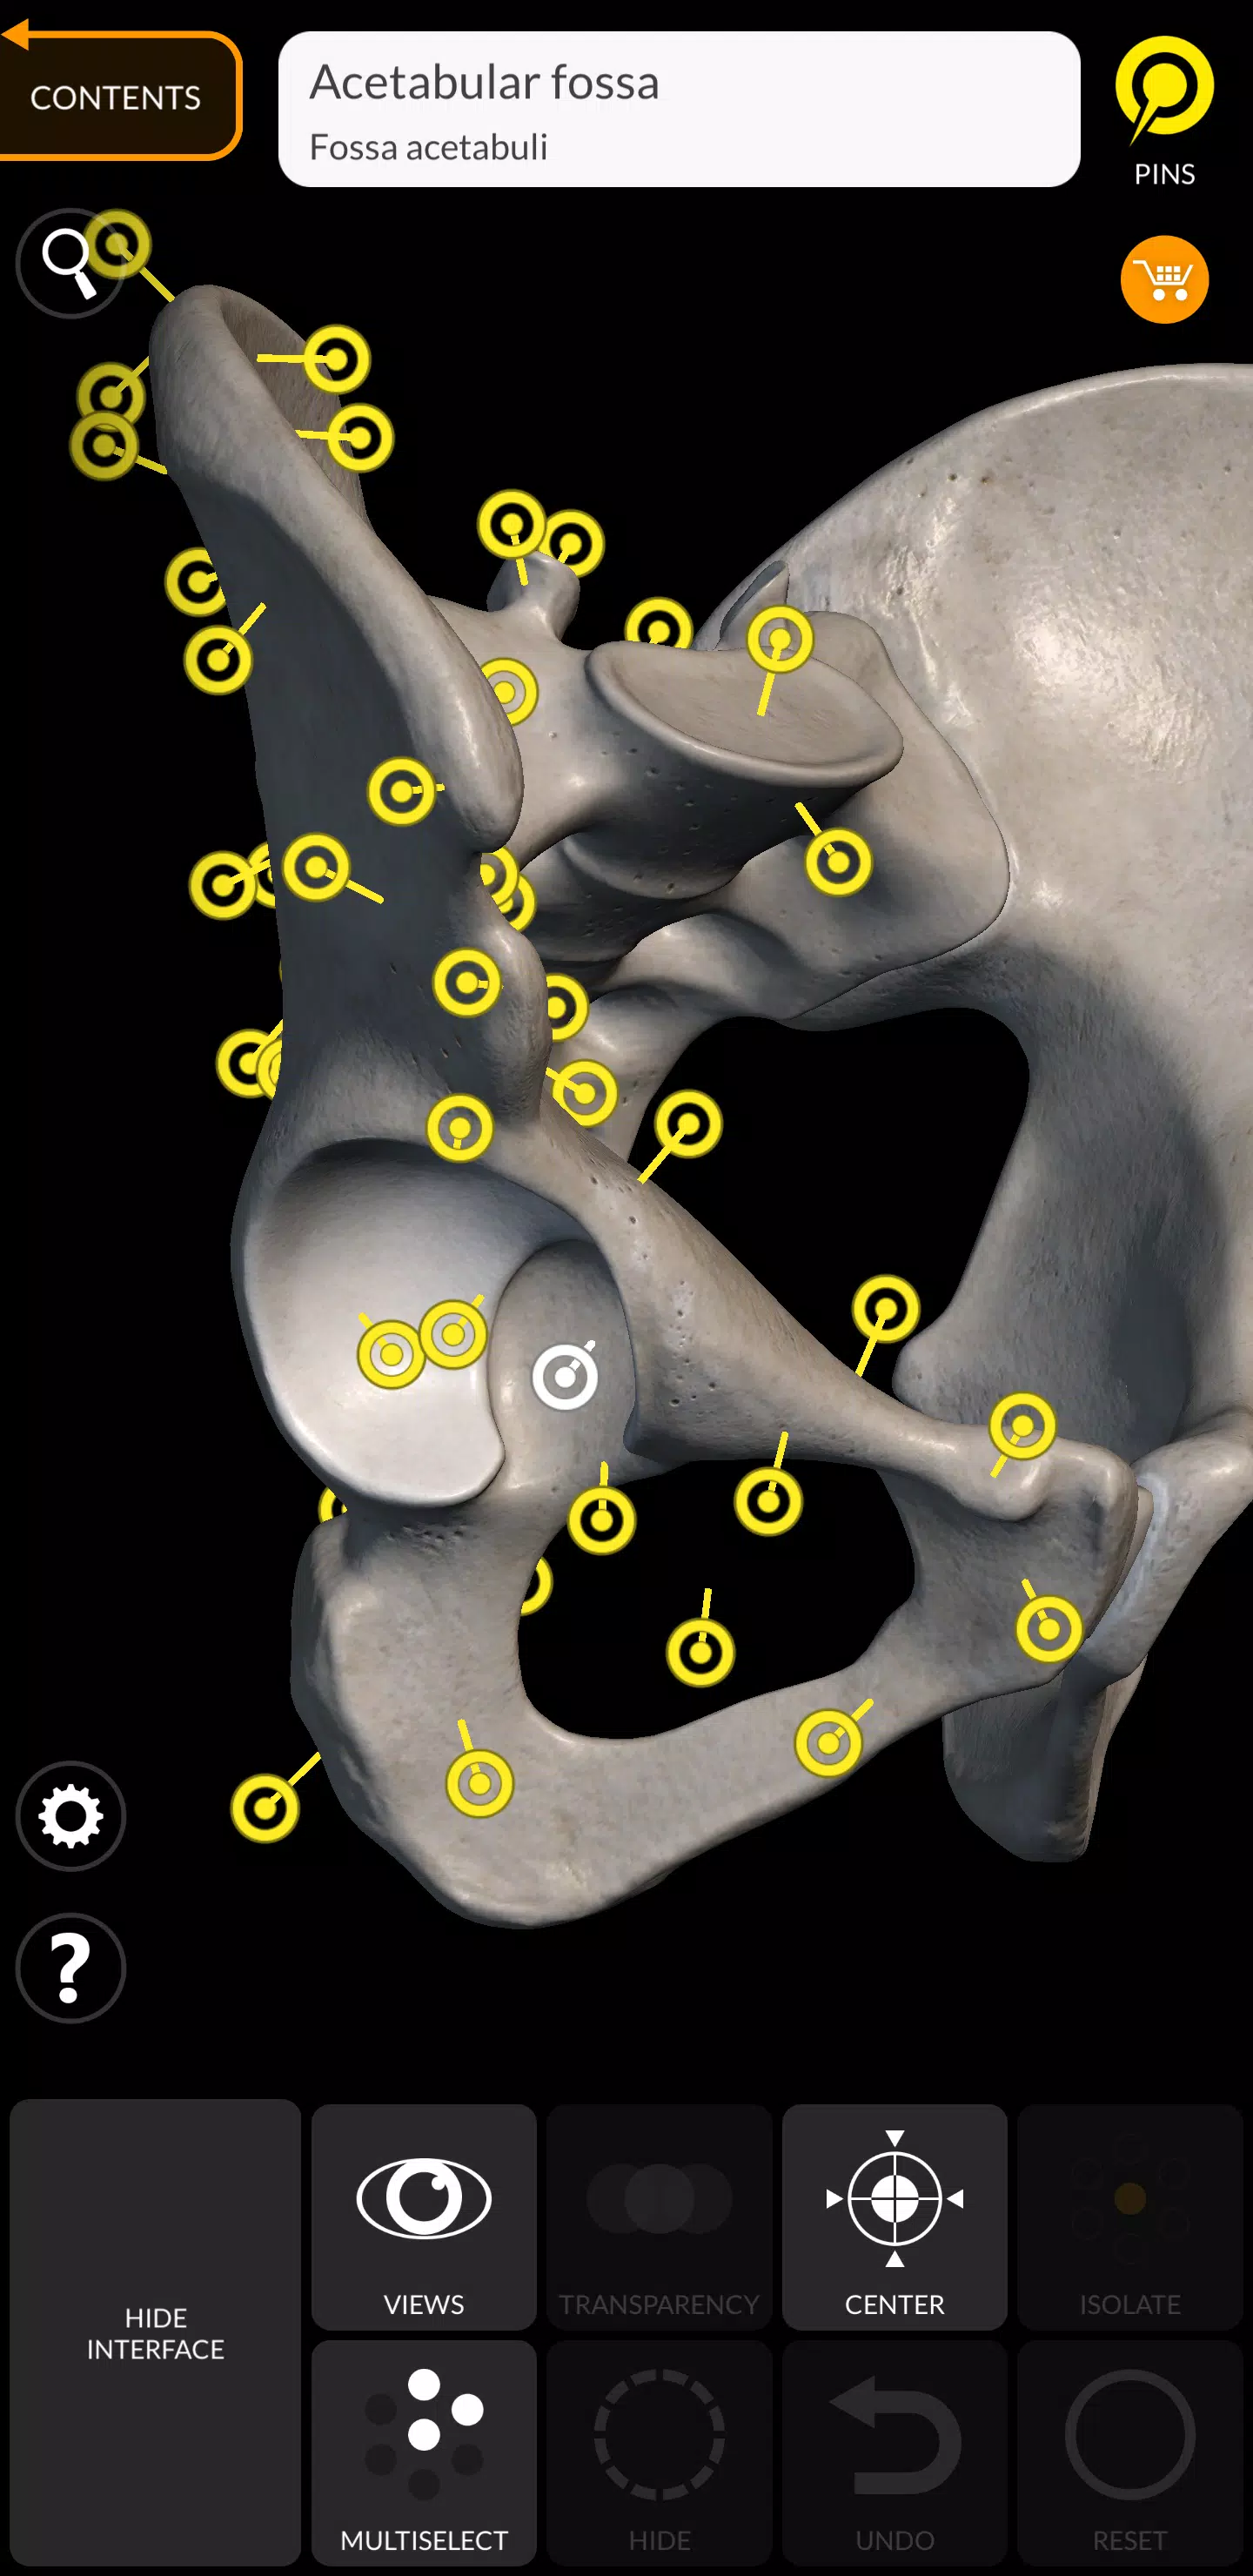

Aplikacja ma przyjazny dla użytkownika interfejs, w którym można wybrać modele lub piny do wyświetlania terminów związanych z określonymi częściami anatomicznymi. Obsługuje 12 języków, w tym łacina, angielski, francuski, niemiecki, włoski, portugalski, rosyjski, hiszpański, chiński, japoński, koreański i turecki. Możesz nawet wyświetlać jednocześnie terminy anatomiczne w dwóch językach, co czyni go nieocenionym zasobem dla międzynarodowych użytkowników i wielojęzycznych uczniów.

- Interaktywne szpilki: wizualizuj terminy związane z każdym szczegółem anatomicznym.

Wsparcie wielojęzyczne

- 12 języków: łacińskie, angielski, francuski, niemiecki, włoski, portugalski, rosyjski, hiszpański, chiński, japoński, koreański i turecki.

- Wybór języka: bezpośrednio wybierany z interfejsu aplikacji.

- Wyświetlanie podwójnego języka: Pokaż terminy anatomiczne w dwóch językach jednocześnie.